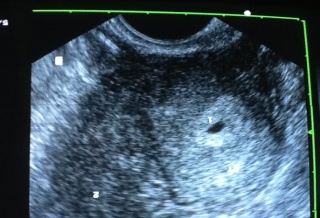

(優活健康網記者杜宇喬/綜合報導)許多人不知道,做試管嬰兒的過程相當繁複且辛苦,一位新北市患有不孕症婦人,曾經在許多醫院做過5次試管嬰兒胚胎都是植左邊子宮都失敗,醫師檢查後發現她有左右兩個子宮,類似上下鋪的結構,這名婦人案例不多見,婦產科醫師蔡鋒博評估這名婦人的情形之後,決定將各放2個胚胎在2個子宮,果真使婦人懷上了兩邊子宮各懷一個胚胎,生下雙胞胎,連醫師也對於成果十分驚訝。

蔡鋒博表示,婦人上面的陰道通往左邊子宮,下面陰道通往右邊子宮,醫師評估後建議,若要做試管嬰兒時最好把胚胎放在右邊子宮,比較有機會著床,但是婦人和她的丈夫堅持決定要把4個胚胎分成左右各放2個在兩個子宮,由於婦人年紀的因素符合放4個胚胎的適應症,植入培育後,過程中也相當順利。病人在驗孕前5天覺得肚子發脹,醫師一聽症狀,趕快叫她來抽血,證實她已經懷了雙胞胎。

醫師表示,這實在是非常少見,更少見的是大部份的雙陰道通常是左右,好像馬路的安全島分開左右兩邊,而她的陰道卻是上下鋪,但是她的子宮是左右分兩邊,實在是不曉得她的子宮跟子宮頸跟陰道是怎麼扭轉的,扭轉成左右的子宮,陰道是上下鋪,而且做試管嬰兒左右子宮各懷一個胚胎,實屬罕見,更是試管嬰兒的案例中相當少見的例子。